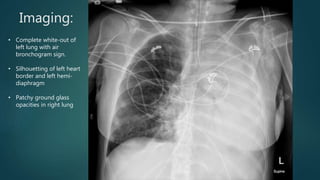

Imaging:

• Complete white-out of

left lung with air

bronchogram sign.

• Silhouetting of left heart

border and left hemi-

diaphragm

• Patchy ground glass

opacities in right lung

Imaging: • Complete white-outof left lung with air bronchogram sign. • Silhouetting of left heart border and left hemi- diaphragm • Patchy ground glass opacities in right lung